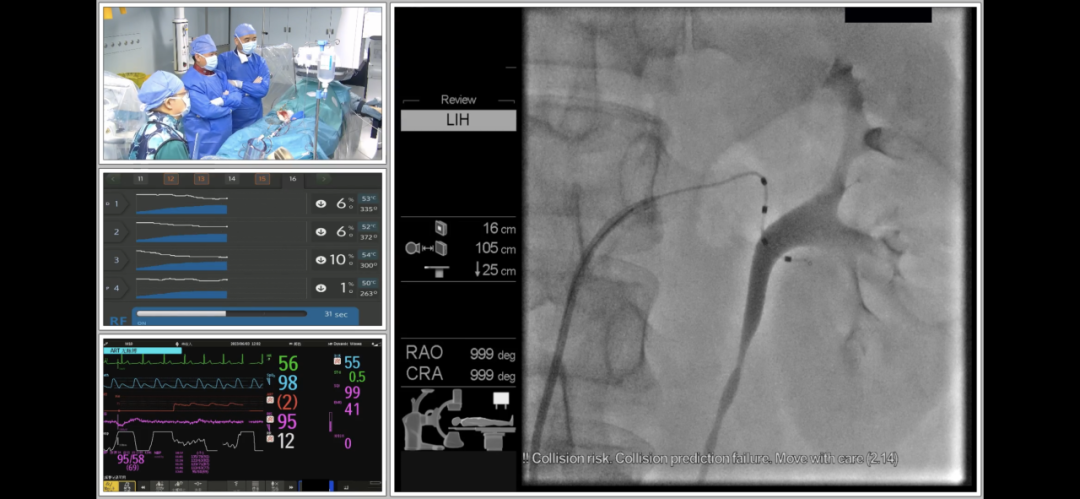

马翔教授和谢翔教授在海南博鳌研究型医院顺利完成RDN手术

术中经股动脉入路,首先对腹主动脉行非选择性造影,以确认肾动脉及副肾动脉开口位置。后通过Launcher导引导管分别对左右肾动脉行选择性造影,在确认血管直径和位置后,决定对分支和主支均进行射频消融治疗。采用由远及近,先分支后主干的消融策略,先后消融了左侧和右侧肾动脉远端分支血管和主干血管,共进行了59个位点的消融,术后造影显示肾动脉血流正常,无痉挛,无狭窄,无明显血管损伤,手术获得圆满成功。